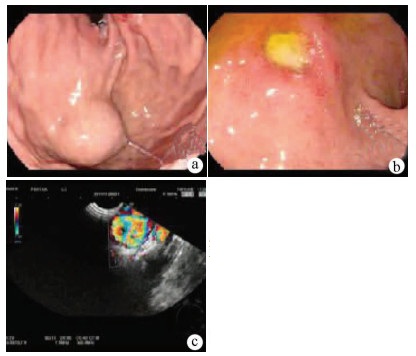

Chinese expert consensus on the endoscopic diagnosis and treatment of biliary fistula (2020, Beijing)

Abstract(1246) HTML (675) PDF (1978KB)(242)

Chinese expert consensus on the endoscopic diagnosis and treatment of pancreatic fistula (2020, Beijing)

Abstract: